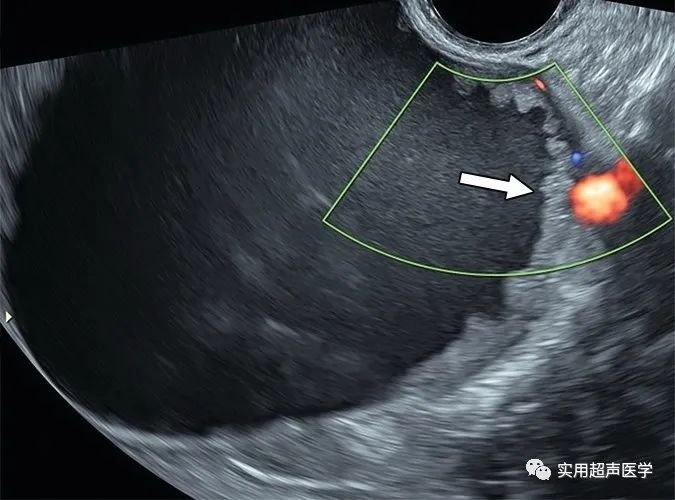

46岁女性,因粘液性囊腺瘤导致盆腔胀满。彩色多普勒超声图像显示右侧卵巢单房囊肿,内壁不规则(箭头)与卵巢-附件报告和数据系统 (O-RADS) 3 类病变一致。壁不规则不会突出囊腔超过 3 mm,因此不符合实性成分或状突起的标准。